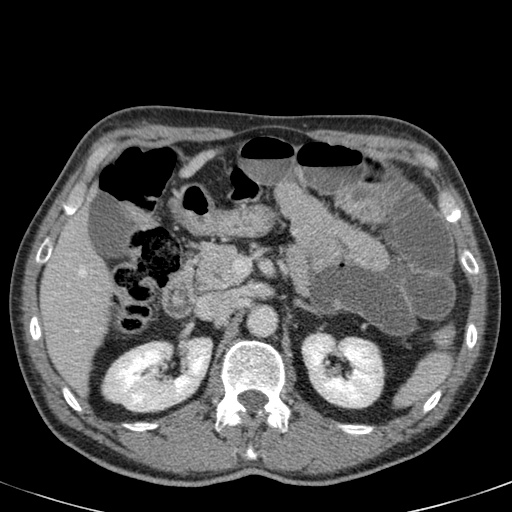

Đây là một bệnh nhân bị tắc ruột non.

Cuộn qua các hình ảnh.

Bạn có thể tìm thấy quai kín và nguyên nhân gây ra nó không?

Khi tiếp nhận bệnh nhân tại phòng cấp cứu với biểu hiện nghi ngờ tắc ruột non (SBO), điều quan trọng nhất chúng ta cần làm, ngoài việc chẩn đoán xác định, là xác định sự hiện diện hay vắng mặt của tình trạng thắt nghẹt.

CT là phương pháp chẩn đoán hình ảnh được lựa chọn trong đánh giá bệnh nhân nghi ngờ tắc ruột non.

Hình ảnh CT của tắc ruột non dạng quai kín phụ thuộc vào hai yếu tố:

- chiều dài đoạn ruột tạo thành quai kín

- hướng của quai ruột so với mặt phẳng tạo ảnh

Nếu quai kín ngắn và nằm trong mặt phẳng tạo ảnh, chúng ta sẽ thấy quai ruột hình chữ U hoặc chữ C.

Một hình ảnh quan trọng khác của tắc ruột dạng quai kín là các quai ruột non giãn xếp theo hình nan hoa với các mạch máu mạc treo hội tụ về một điểm trung tâm.

Hình ảnh này hầu như luôn do xoắn ruột non gây ra.